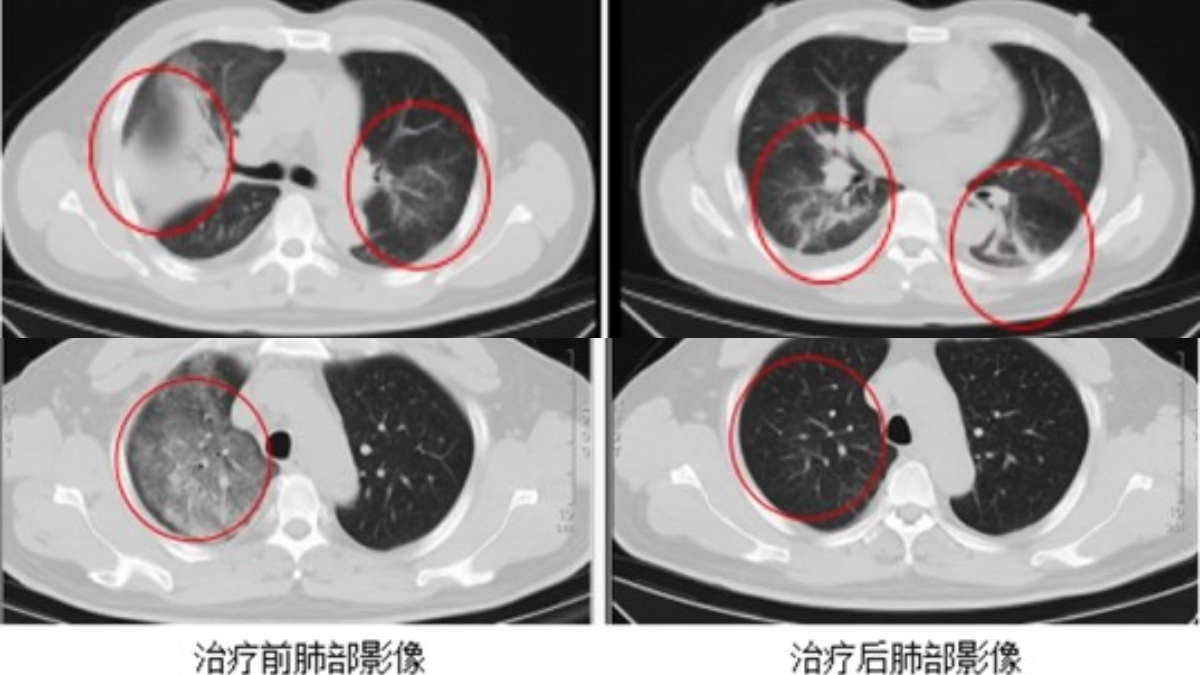

中国江苏去年也确诊一例“Q热”病患者,就诊时,其双肺已经出现大面积病变。